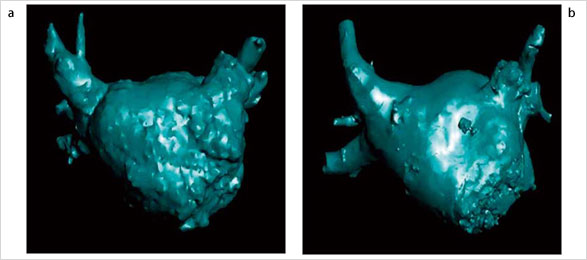

また最新では,心臓CTデータによるマッピングに替わり,血管撮影装置の回転撮影より得られた3次元画像(3D-ATG)を使用したマッピングも可能となっている。図6のように,心臓CTと遜色のない画質で左心房の描出が行える。3D-ATGは,心臓CTによるEP Navigatorのように位置合わせの必要がなく,自動的に透視画像にオーバーレイされるため,正確で迅速な治療の支援となる。  今後,わが国でも増加が予想されるアブレーション治療に対して,EP Navigatorはさまざまな形で貢献できると考えられる。特に,手技時間の短縮によりスループットが向上し,潜在的な患者さまを含めた多くの症例を治療の対象にできることはメリットであろう。

図6 3D-ATGによる左心房の描出(a)とCTスキャナによる左心房の描出(b)